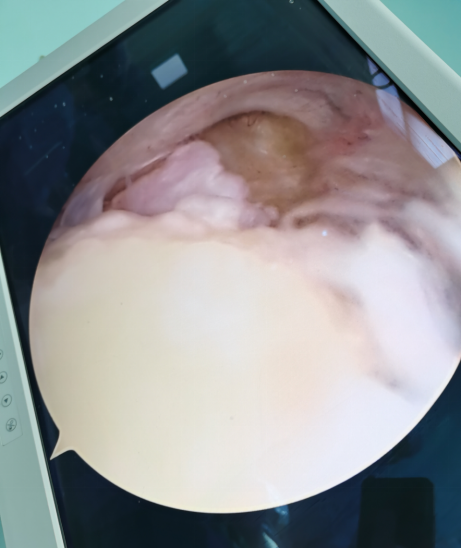

肘关节镜下术中图可见游离体及异位骨化

患者男,因右肘关节疼痛伴屈伸受限约2年,严重影响了工作和生活,曾辗转周边多家医院就诊,均建议给予切开手术,后患者多方打听到齐医附属三院微创骨科专家孙文才主任专业做微创手术后,到我院就诊,肘关节MRI提示右肘后鹰嘴窝处异位骨化、关节游离体形成,入院后经孙文才主任及其团队充分讨论,决定对其实施肘关节镜微创治疗手术,采用肘后内外侧标准入路,切口仅长约0.5cm,术中创伤小、出血微量,手术实施顺利,成功将游离体及异位骨化骨块取出,术后肘关节功能恢复好,患者对治疗效果非常满意。